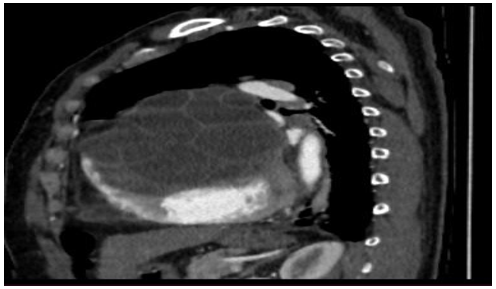

A computedtomography (CT) chest scan revealed (Figures 3-7):

• Evidence of bilaterallobar and segmental pulmonaryembolism on the right in addition to segmental pulmonary embolism localized to the leftside. The seembolic changes exhibited a chronic appearance without any indication of pulmonary parenchymal infarction. (Figures 6-7). These finding scorrelated with the observed increase in D- dimer levels.

• 2 large bilater alanterior mediastinal and para- cardiac formations, likely of hydatid origin, are

causing extrinsic compression of the cardiaccavities (Figures 3 – 5):

The structures in question are characterized by multi-walls, a regular outline, distinct margins, and an enhanced wall definition following the injection of contrast medium.

The dimensions on the right are 93 x 114 mm and extend over 119 mm;whileon the left, the measurements are 119 x 78 mm extanding over 140 mm.

Posteriorly, these structures exertcompression on the adjacent lungparenchymaresulting in passive collapse.

• Absence of pleural effusion.